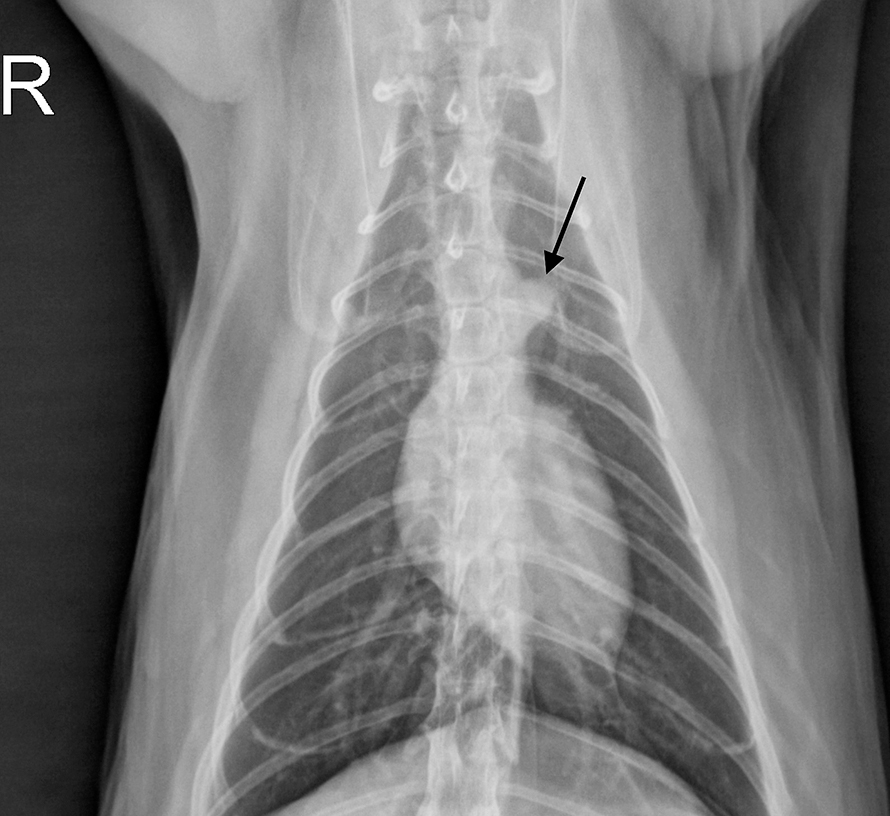

From journals.sagepub.com

Radiographic features of cardiogenic pulmonary oedema in cats with left Cat Chest Heart Your cat's age and breed may help your veterinarian diagnose its heart disease. The most common types of congenital heart disease in cats are heart valve malformations, ventricular septal defect (vsd),. This can result in an accumulation of fluid in the abdomen, chest cavity, liver, or limbs. Cats get many kinds of heart disease but the most common is called. Cat Chest Heart.

Diagnostic accuracy of the vertebral heart score and other radiographic Cat Chest Heart A common clinical sign of. Most cats do not show any clinical signs of heart disease until it progresses. Cats get many kinds of heart disease but the most common is called cardiomyopathy, according to the cornell feline health center. The most common types of congenital heart disease in cats are heart valve malformations, ventricular septal defect (vsd),. This is. Cat Chest Heart.

(a) Right lateral and (b) ventrodorsal thoracic radiographs in a kitten Cat Chest Heart We’ve put together a guide to help if you are concerned about your cat’s heart health. The clinical signs of heart disease in cats differ depending on the type. The most common types of congenital heart disease in cats are heart valve malformations, ventricular septal defect (vsd),. Your cat's age and breed may help your veterinarian diagnose its heart disease.. Cat Chest Heart.